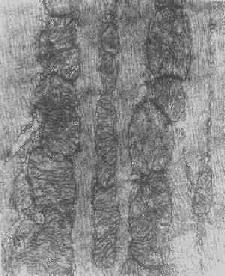

根据细胞损伤的种类和性质,可在线粒体基质或嵴内形成病理性包含物。这些包含物有的呈晶形或副晶形(可能由蛋白构成),如在线粒体性肌病或进行性肌营养不良时所见(图1-12);有的呈无定形的电子致

线粒体内晶形包含体(进行性肌营养不良症)

图1-12 线粒体内晶形包含体(进行性肌营养不良症)

密物,常见于细胞趋于坏死时,乃线粒体成分崩解的产物(脂质和蛋白质),被视为线粒体不可复性损伤的表现。线粒体损伤的另一种常见改变为髓鞘样层状结构的形成,这是线粒体膜损伤的结果。